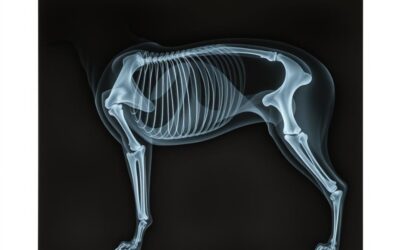

Röntgen kĺbov psa – Všetko, čo o tom potrebuješ vedieť!

Zistite dôležité informácie o röntgene kĺbov psa, kedy je potrebný a ako pomáha včas odhaliť zdravotné problémy vášho miláčika.